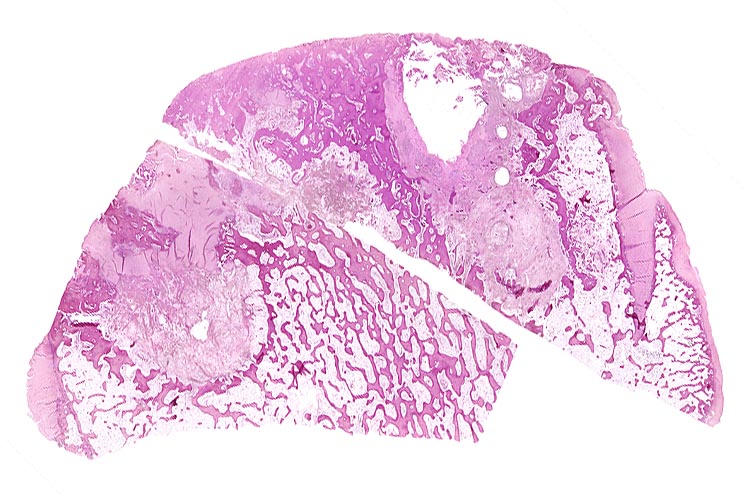

Morphologische Merkmale:

• Deformierte Gelenkfläche.

• Weitgehendes Fehlen des hyalinen Gelenkknorpels.

• Sekundäre Sklerose der freiliegenden Spongiosa mit Anbau von breiten Faser- und Lamellenknochensäumen an die alten Bälkchen.

• Leichte Osteoporose in der craniolateralen Entlastungszone.

• Herde von metaplastischem Faserknorpel in der Gelenkfläche.

• Randosteophyt, welcher über Resten des dort noch vorhandenen Gelenkknorpels entstanden ist (Verdoppelung des Knorpels).

• Nekrosebezirk in der Spongiosa (Geröllzyste) umgeben von einem Granulationsgewebssaum und Narbengewebe.